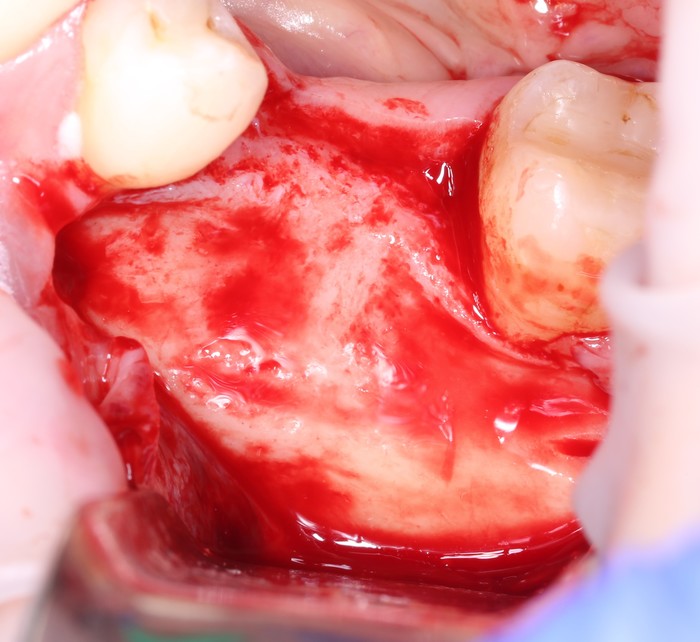

Челюстная кость, как, впрочем, любая другая, неоднородна по своей структуре. В её наружном слое, называемом кортикальной (или компактной) пластинкой, преобладает межклеточное вещество с высокой степенью минерализации. Во внутренней части, губчатом веществе, наоборот, межклеточного вещества не так уж и много, зато присутствует большое количество клеточных элементов, сосудов и нервов.

Поэтому ультразвуковым наконечником необходимо эту пластинку убрать.

Так она выделяется:

А удаляется теми же остеотомами: